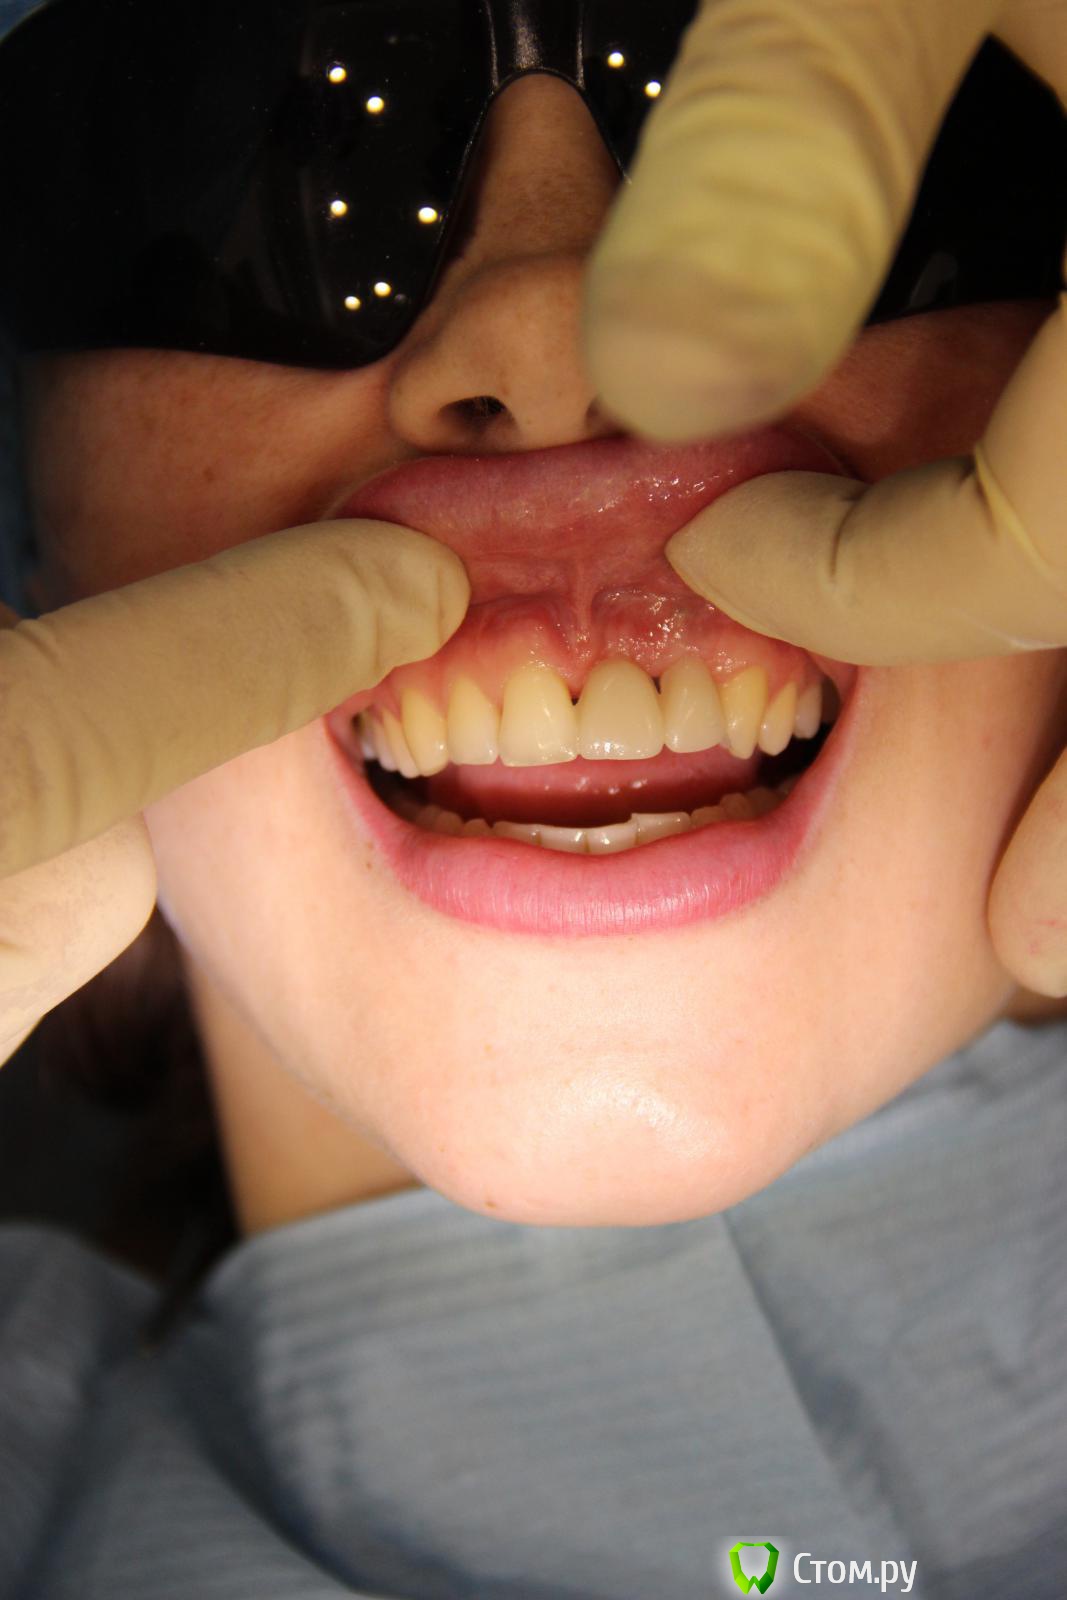

Abuk Опубликовано 3 августа, 2014 Поделиться Опубликовано 3 августа, 2014 Добрый день,коллеги.Горит,помогайте! Года 2 назад,когда я был молод,красив и малоопытен)),консультировал пациентку,на предмет восстановления имплантатами двух отсутствующих зубов:2.1,2.2; на месте которых висел композитный пртез. Отрофия кости была заметна невооруженным глазом,КТ подтвердило. Начинали с 3D пластики.Старые фото, пока, не нахожу((( Ширина кости была около 3 мм по 11-13 мм гребню.После операции ,спустя 4 месяца,пациентка ушла в декрет и пропала на 2 года.Ныне сделав рентген - шаблон,отправил на КТ(.Ошибки я учел,по поводу костной пластики).Недостаток в верхушке гребня и воостановление десневого сосочка-задачи,которые предстоит решить.Посоветуйте:возможно ли1.без повторной агрессивной костной пластики2.или можно ограничиться только работой с мягкими тканями???????? Ссылка на комментарий